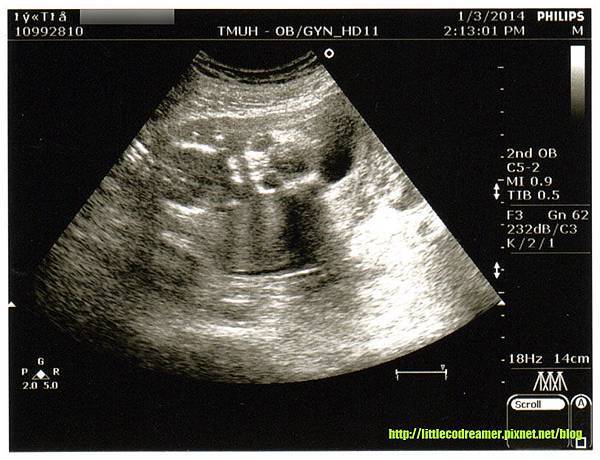

↑邁入第五個月,頭骨已經成型,臉還沒開始長肉。我還是覺得很可愛。

相隔一個月不見小CO,加上想讓媽媽看看寶貝外孫的近況,還是決定自費照超音波。小CO心跳強力穩健,也有按照進度長大,我先前因害喜而對營養不足的擔憂可以暫時拋開。透過超音波已經可以清楚看到成型的頭骨,但此週數尚未開始長臉部的肉。看起來有那麼一點外星人的味道,即使如此我還是覺得小CO很可愛。